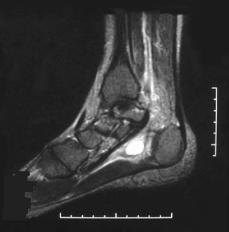

Define the anatomy of the tarsal tunnel?

Anatomy defined by

What is in the tarsal tunnel?

Describe how would you release the tarsal tunnel?